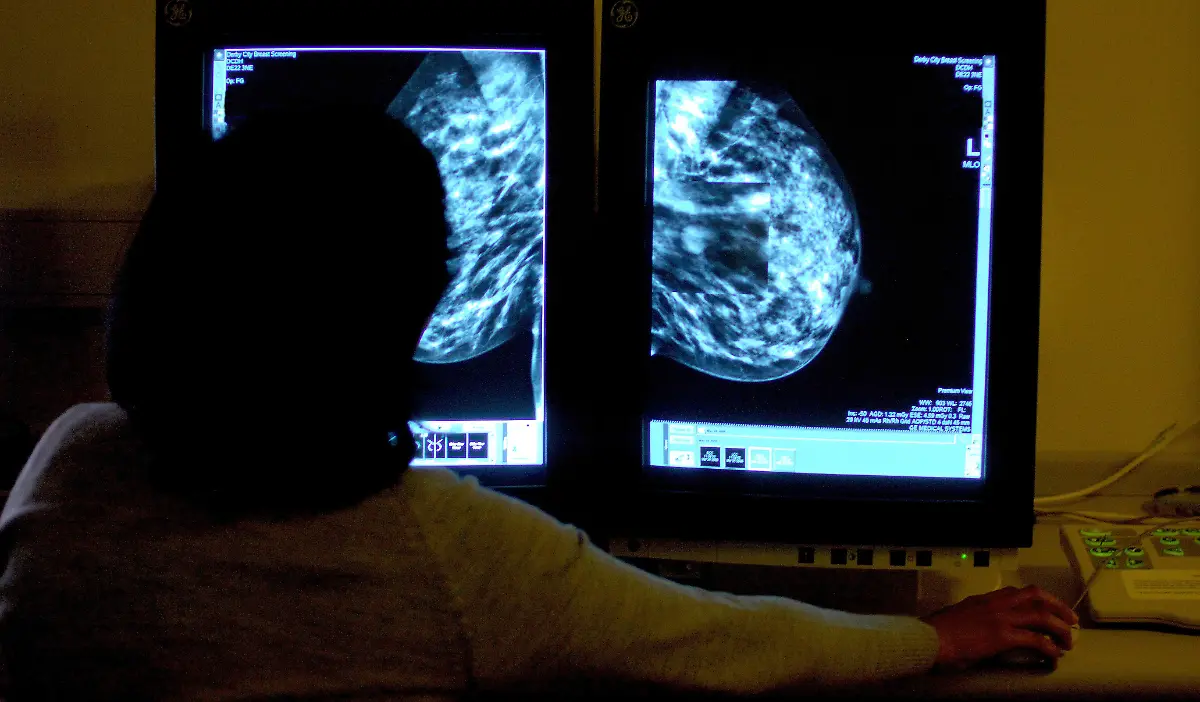

Er war ein Revolutionär der Medizintechnik: Der Physiker Wilhelm Conrad Röntgen entdeckte 1895 zufällig die X-Strahlen, was nicht nur für die Diagnostik in der Medizin ein Meilenstein war. Später wurden die Strahlen und das Verfahren nach ihm benannt. Röntgen starb vor 100 Jahren in München.